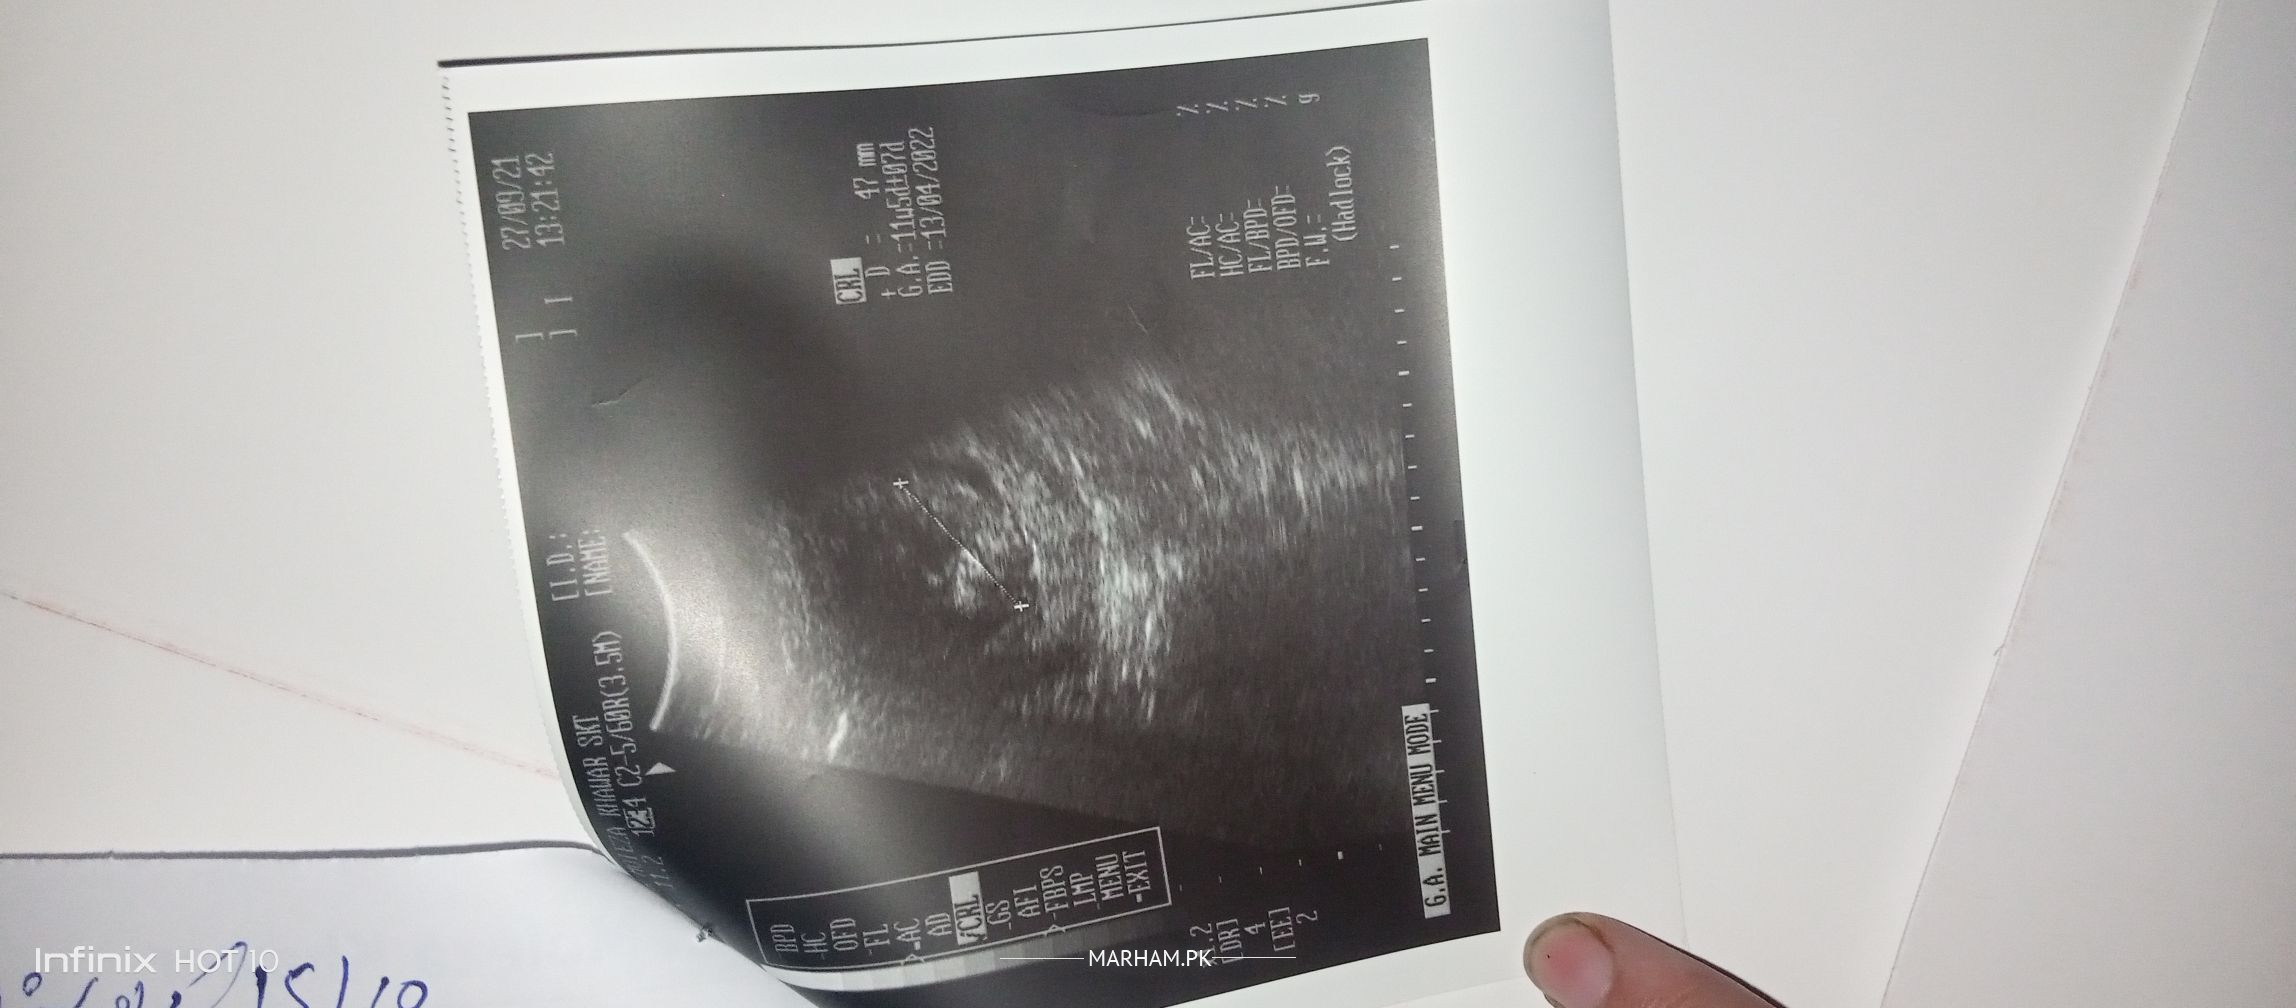

A.o.A ma 12 week pregnant ho ma doc ko 11 weeks 3 days ma check krwaya .. Woh kah rhi sb normal ha likn ap ka placenta nchya ha likn 2 months ka andr woh apni jaga pa ja skta ha jb baby grow krya ga ... but i am afraid sb thk rhya ... Ap plz mri ultrasound report b check kr lay mra baby ka size wgra to thk ha na growth thk ho rhi week ka hisab sa plz doc i am thankful to you .

need proper scan report and detailed history

i am first time mom ... and this is my first scan

then u should get an appointment for proper assessment